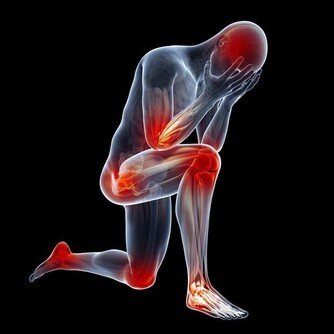

眾所周知,一旦尿酸高了,會引發全身性疾病,首當其衝的就是關節疾病,對於腎臟、血管等都會有不同程度的損害,還會影響血糖引發糖尿病等等。

如果尿酸高了,晚上睡覺時身體會出現下面幾種情況,千萬不要忽視!

3、下肢水腫

晚上睡覺的時候身體裡面的尿酸含量是最高的,所以腎小球容易被堵塞,甚至會出現壞死情況,身體裡面的水分沒有辦法很好的排出,容易堆積在身體裡面,這樣就會出現水腫情況,特別是下肢水腫以及眼瞼水腫的情況是比較嚴重的。

4、腰疼

身體裡面的尿酸如果堆積很多,腎臟就會出現非常嚴重的負擔,容易導致腎結石問題出現,腎臟出現問題就會影響到腰部的健康,容易出現疼痛感覺,情況嚴重的話還容易導致失眠症狀出現,所以一定要特別注意。